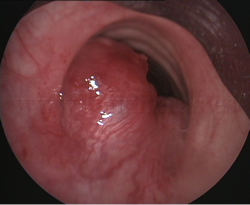

Cuerpo

extraño endobronquial |